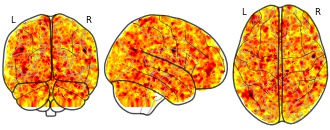

License information was derived automaticallyDescriptionA collection of 9532 brain maps. Each brain map is a 3D array of values representing properties of the brain at different locations.

The individual Brain Charting (IBC) Project is using high resolution fMRI to map 13 subjects that undergo a large number of tasks: the HCP tasks, the so-called ARCHI tasks, a specific language task, video watching, low-level visual stimulation etc. The native resolution of the data is 1.5mm isotropic. Their main value lies in the large number of contrasts probed, the level of detail and the high SNR per subject. This dataset is meant to provide the basis of a functional brain atlas. We upload here smoothed individual SPMs. The uploaded maps comprise session-specific and fixed effects across maps acquired with AP and PA phase encoding directions.

Note that Neurovault collection #4438 is a subset of that one. In the present collections, some details have been fixed, including mroe accurate and unique file naming.